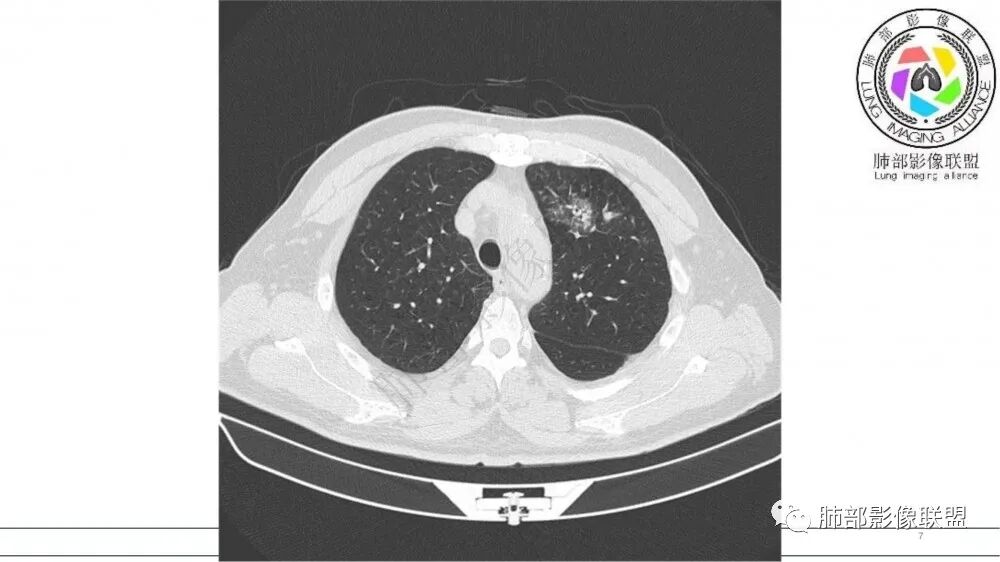

左肺上叶前段支气管内铸形生长软组织影,增强后均匀强化,远侧见斑片状磨玻璃影。考虑恶性病变,粘表?粘液腺?

老年男性,左肺上叶前段支气管内铸形阴影,增强后病灶不均匀强化,内部有坏死?远端可见斑片状阴影(阻塞性肺炎)。考虑恶性病变,老年人,鳞?类癌?粘表不能排除。

左肺上叶前段支气管杵状指样扩张,内见实性组织阻塞性,并强化明显,边缘饱满,周边多发小斑点影,小花小草征,老年男性,长期吸烟史,方向恶性,首选支气管内浸润鳞Ca可能性大。

男,70岁,吸烟史,咳嗽,胸闷憋气一个月,左肺上叶不规则形软组织密度影,病灶沿支气管走形,周围见粟粒及棉絮样稍高密度影,增强扫描病灶内见少许坏死,考虑鳞癌可能,鉴别结核。

老年男性,肺气肿,吸烟史,左肺上支气管腔内铸型高密度影,呈指套状,远端多发树芽,增强不均匀强化,考虑鳞癌,鉴别小细胞癌

B3指套征,常规不是鳞癌就是ABPA,有强化丶血管造影征,倾向于鳞癌

老年男性,长期吸烟史。左上肺前段沿支气管走形的指套样病变,增强可见病灶强化(排除结核、ABPA(也无气喘症状)),远端多发点状高密度影。考虑恶性肿瘤,鳞癌可能性大。

指套征,扩张支气管内软组织强化,远侧肺野阻塞性炎,纵隔、左肺门肿大淋巴结;老年男性,吸烟,考虑鳞癌,鉴别小

指套征:是影像征象,胸部平片表现为手指状密度增高影,以肺门为中心呈放射状分布,CT显示扩张支气管内低密度黏液栓形成或实性病变,呈管状、树枝状或卵圆形密度增高影;支气管扩张伴近端梗阻时,扩张支气管内部黏液分泌物不能排出而形成。可以伴随远端空气潴留征、阻塞性炎症。

研究报道,中心型 SCLC 经 CT 扫描后通常支气管表现为鼠尾样狭窄,肺门或纵隔肿块明显,由于肿块沿管壁生长表现为顺延支气管形态的不规则形状。病灶相对特征性影像学表现比如鸭蹼状、腊肠状、葫芦状及葡萄状改变,可以出现血管包埋,很少有空洞、空泡,较少引发肺不张,阻塞性炎症成都较轻。与一般肺癌比较,恶性程度高,侵袭力强、病灶很小就容易远处转移!Herzberg 等[19]研究指出,20%以上 SCLC 倍增时间短,预后不良。